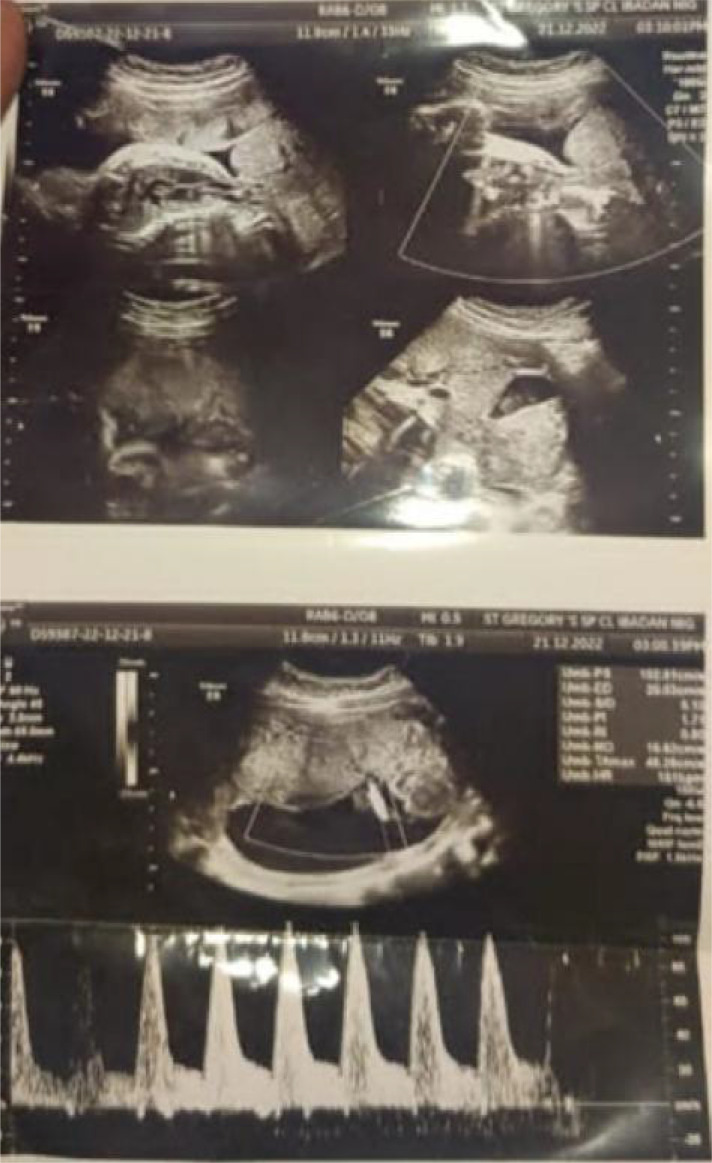

Case presentation: We report a case of sonologically delayed diagnosis of BSA which was confirmed post-delivery following histopathological examination and we reviewed relevant literature regarding this phenomenon. Sonographic features of the foetus included a wide anterior abdominal wall defect (omphalocele) with protrusion of the liver into the amniotic cavity. The umbilical arteries show normal calibre, flow, velocimetry, and spectral waveform.